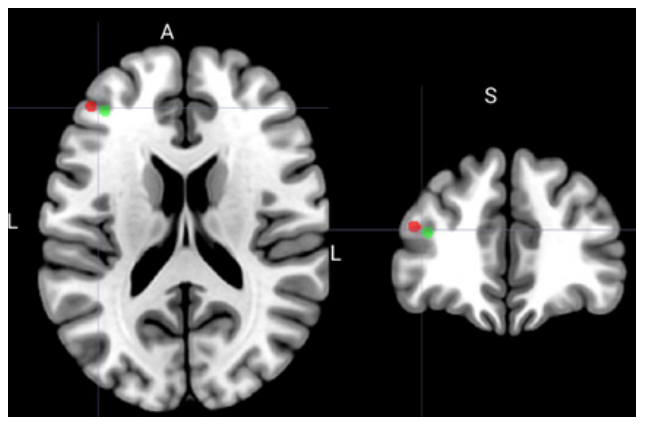

Рис. 4. Сопоставление средних положений мишеней в ДЛПФК в пространстве MNI по данным настоящего исследования (красный) и работы [26] (показаны зеленым). В работе [26] средняя точка определялась среди мишеней в ДЛПФК, найденных как пики независимых компонент индивидуального сигнала фМРТ покоя, визуально идентифицированных как сеть FPCN